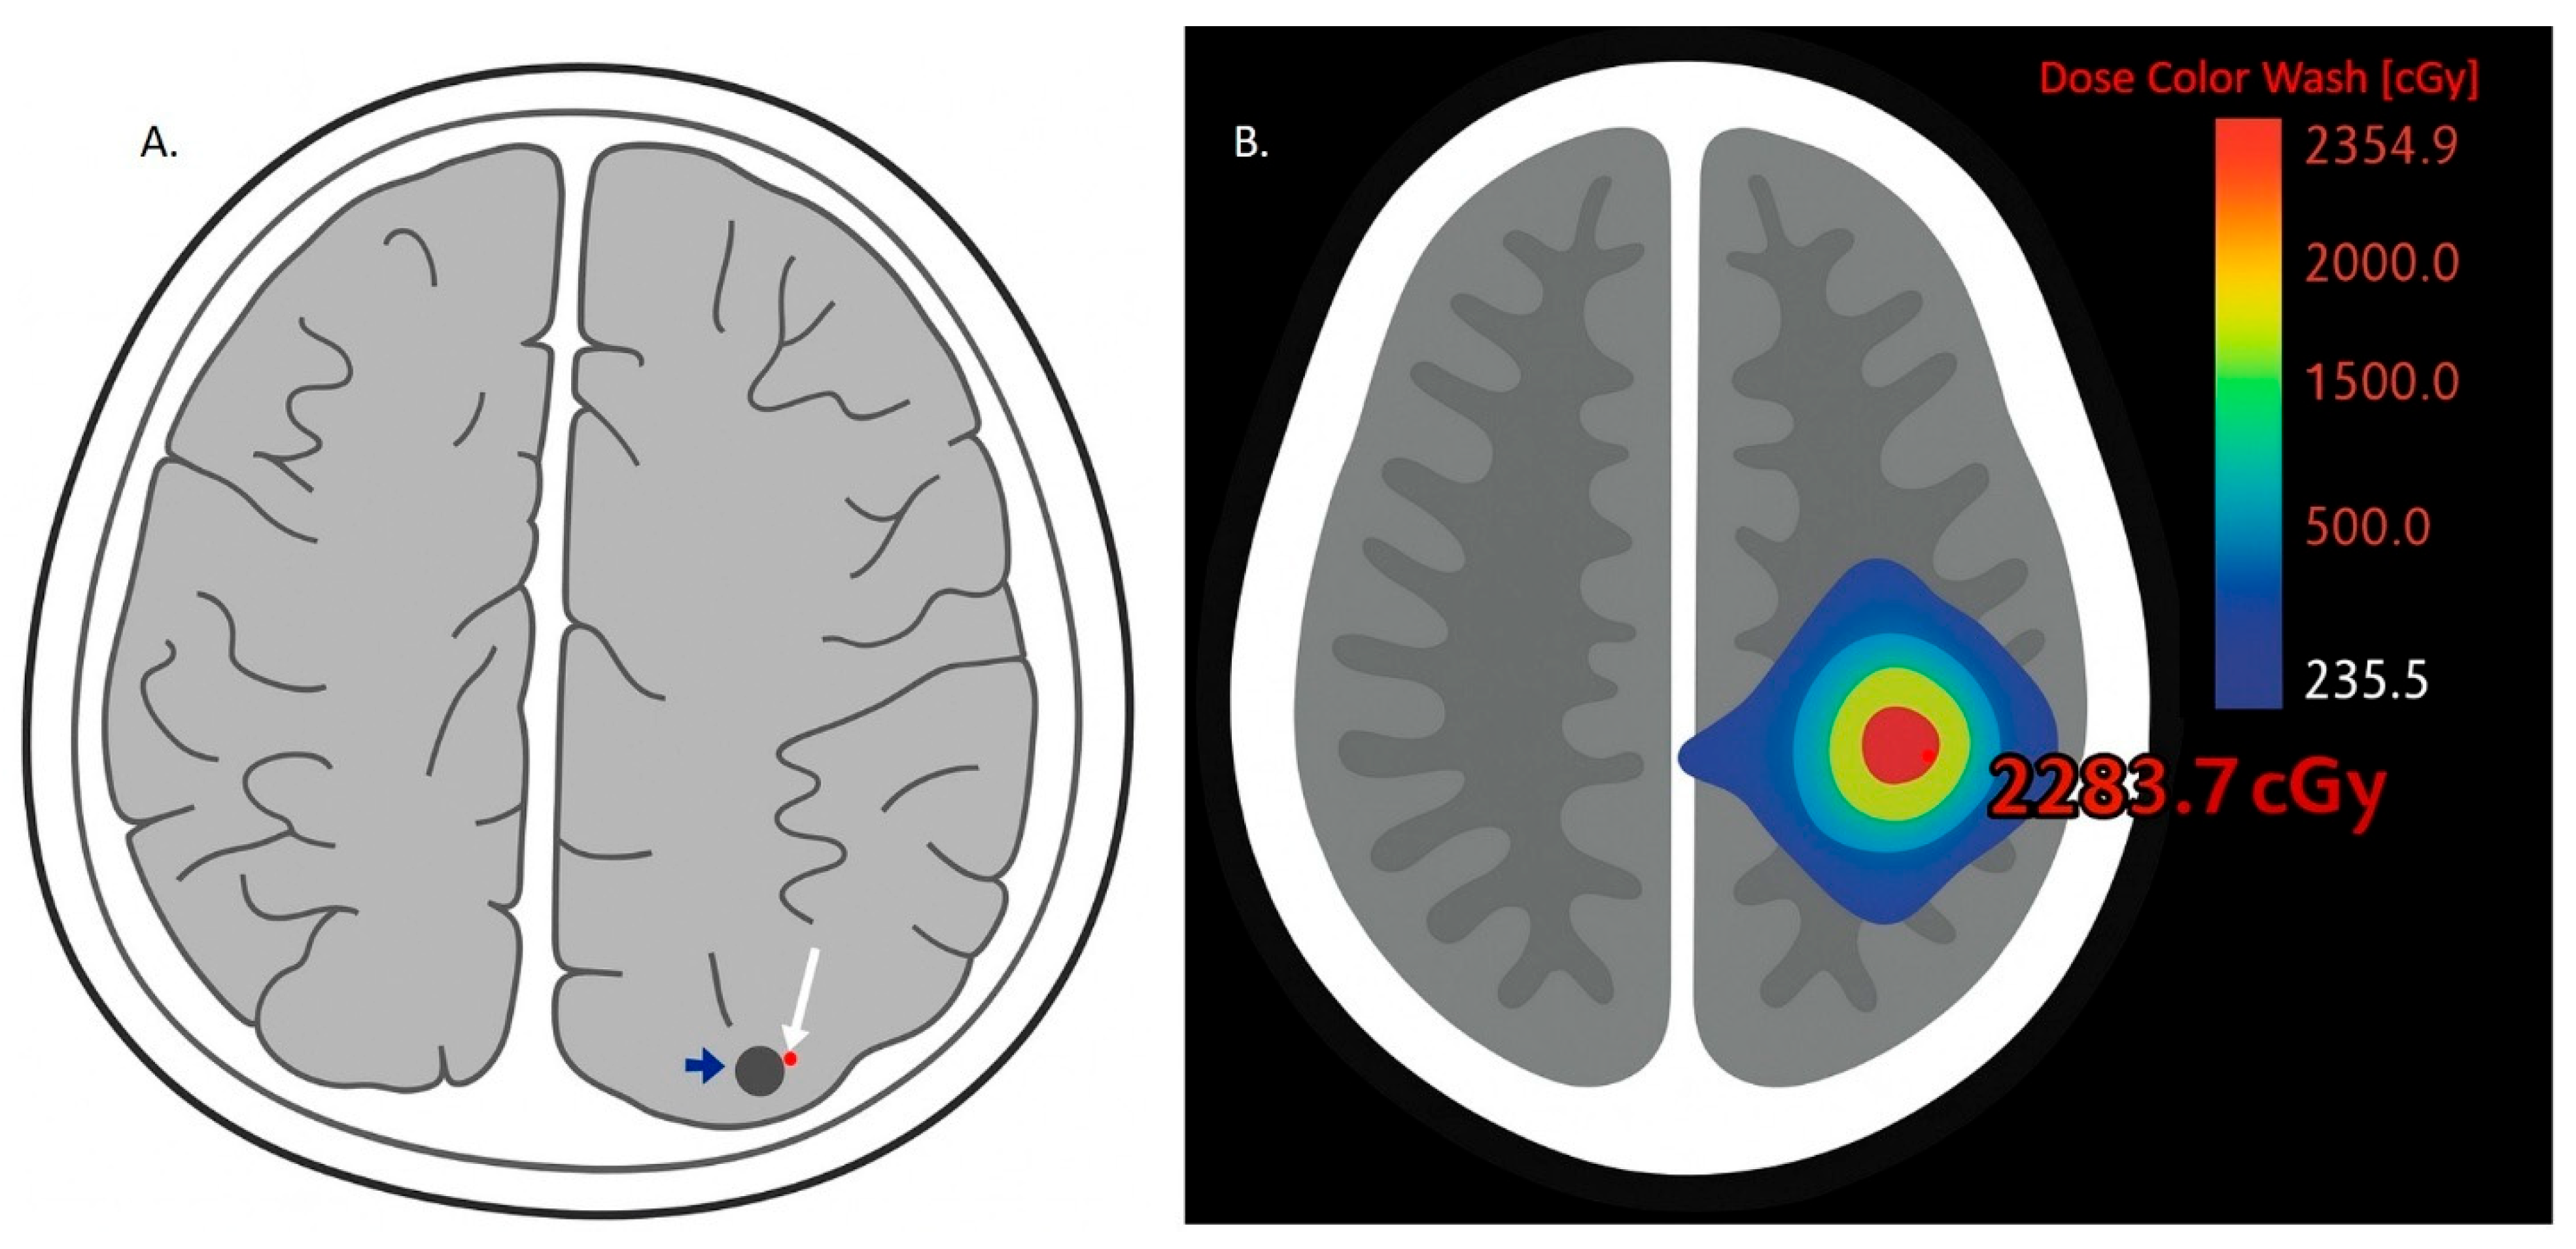

5.5. Stereotactic Radiosurgery (SRS) and ICIs for Treatment of Brain Metastases from NSCLC